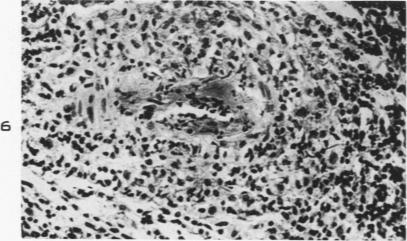

Asymptomatic focal arteritis of the appendix; 88 cases.

Am J Pathol. 1951 Mar-Apr;27(2):247-63.